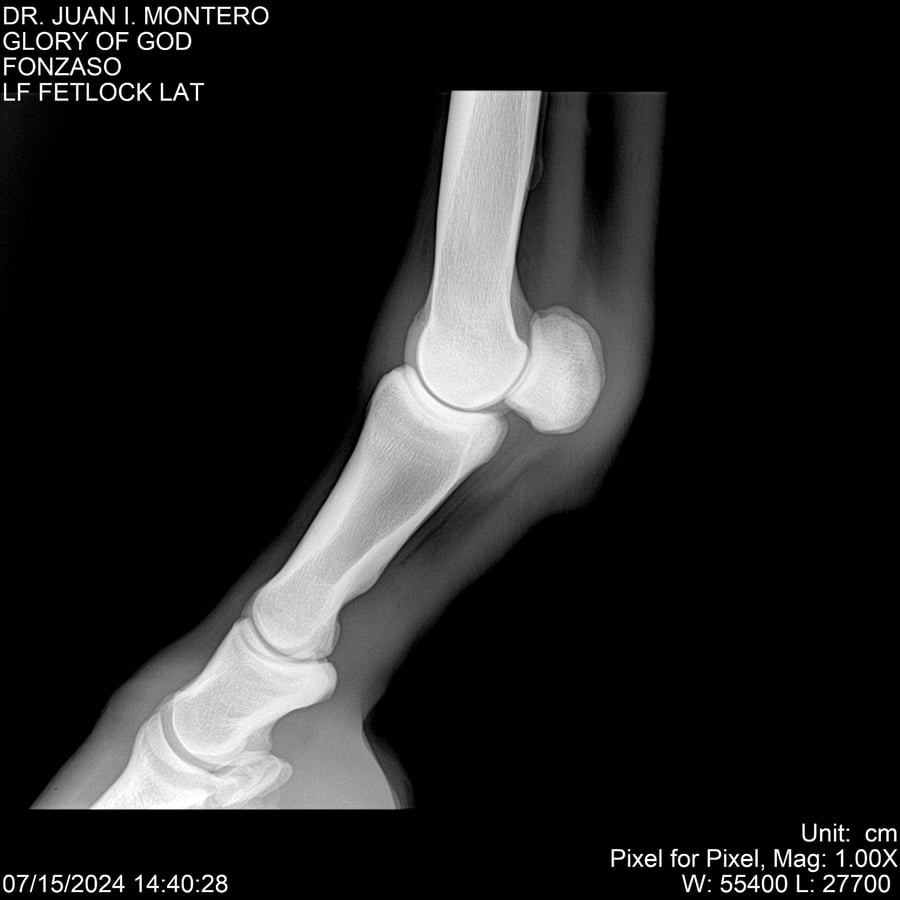

LOTE 10, GLORY OF GOD 🔥 🔥 🔥 Lote Anterior Volver al remate Lote Siguiente Ficha Contacto Montevideo - Ficha del Lote Identificador: #281389 Categoría: Yeguarizos Montevideo - 115 Visualizaciones ClicData Contacto Empresa: Abelenda N. R., Walter Hugo Nombre*: Teléfono* : E-mail* : Mensaje Enviar Registrese gratis Este contenido Exclusivo está disponible sólo para usuarios registrados Ingresar